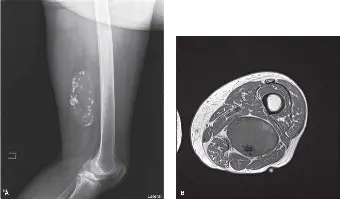

الأشعة السينية (X-ray)

• الغرض: تُعد الأشعة السينية أول خطوة في التصوير، وتُستخدم لاستبعاد أي مشاركة عظمية مباشرة أو تفاعلات في سمحاق العظم (periosteal reaction) أو تآكل في قشرة العظم.

• النتائج: في حالة السيد "ج. أ."، أظهرت الأشعة السينية كتلة نسيج رخو كبيرة شفافة نسبيًا للأشعة (radiolucent) في الفخذ الخلفي، متوافقة مع آفة دهنية. لم يكن هناك أي دليل على تأثير على العظام أو تكلسات داخل الكتلة. على الرغم من أنها قد تشير إلى ورم دهني حميد، إلا أن حجمها وموقعها العميق استدعى المزيد من التصوير المتقدم.

التصوير بالرنين المغناطيسي (MRI) – المعيار الذهبي

• الغرض: يُعد التصوير بالرنين المغناطيسي هو الطريقة التصويرية الحاسمة لتحديد مرحلة الورم محليًا. يوفر تفاصيل لا مثيل لها حول حجم الورم وامتداده ومشاركته في الأنسجة المحيطة وعلاقته بالهياكل العصبية الوعائية الدقيقة. يتم إجراؤه عادةً مع وبدون صبغة الغادولينيوم الوريدية.

• النتائج:

• تم تحديد كتلة كبيرة متعددة الفصوص، يبلغ قياسها حوالي 10.5 × 8.0 × 7.2 سم، في الجزء الخلفي الإنسي من الفخذ الأيمن.

• كانت الكتلة ذات إشارة عالية بشكل سائد في تسلسلات T1-weighted، وأظهرت قمعًا خفيفًا للإشارة في تسلسلات إشباع الدهون (fat-saturated sequences)، مما يشير إلى مكون دهني كبير.

• لوحظت حواجز سميكة متعددة معززة بالصبغة، وعدة مناطق عقدية بؤرية غير دهنية داخل الكتلة. كانت هذه العقد متساوية الإشارة للعضلات في T1، وذات إشارة عالية في T2، وأظهرت تعزيزًا غير متجانس بعد حقن الصبغة.

• كان الورم يلامس العضلتين شبه الغشائية والمقربة الكبيرة بشكل وثيق، مع وجود دليل على إزاحة طفيفة ولكن دون غزو واضح للعضلات نفسها.

• تم إزاحة العصب الوركي والحزمة الوعائية العصبية الفخذية السطحية إلى الأمام والجانب بواسطة الكتلة، لكنها لم تظهر عليها علامات الغزو المباشر.

• لم يكن هناك تآكل مباشر في قشرة عظم الفخذ أو غزو لنخاع العظم.

• كانت هذه النتائج تشير بقوة إلى ساركوما شحمية جيدة التمايز (ورم شحمي غير نمطي - ALT).

صورة بالرنين المغناطيسي تظهر الورم الشحمي الخبيث في الفخذ الخلفي

• التفسير: إن وجود حواجز سميكة ومكونات غير دهنية معززة بالصبغة داخل ورم دهني في موقع عميق يثير شكوكًا كبيرة حول الساركوما الشحمية، ويميزها عن الورم الشحمي الحميد.